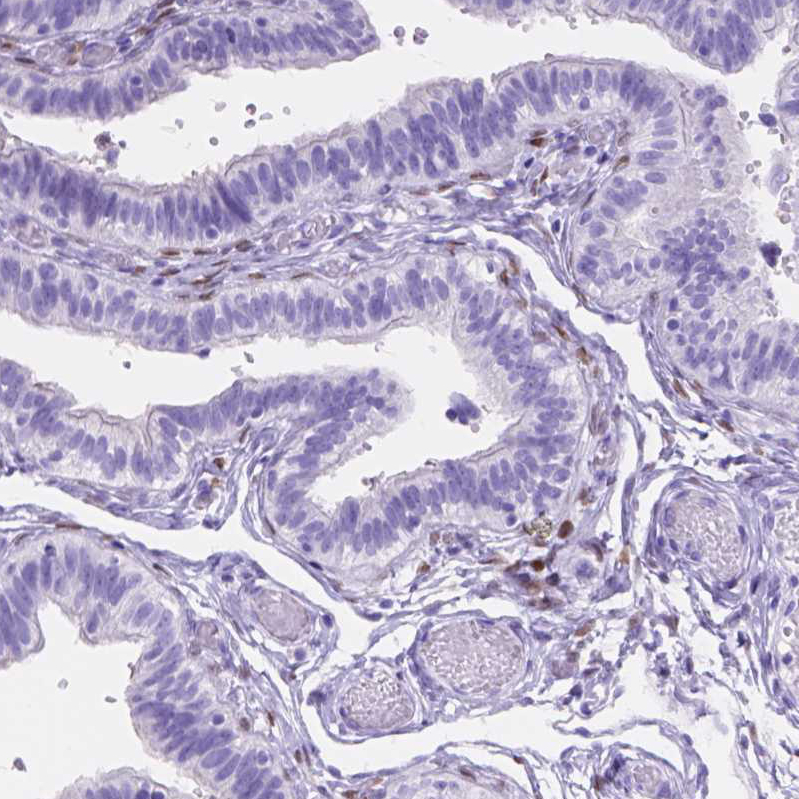

Immunohistochemistry analysis in human ovary and skeletal muscle tissues using HPA069613 antibody. Corresponding FOXL2 RNA-seq data are presented for the same tissues.